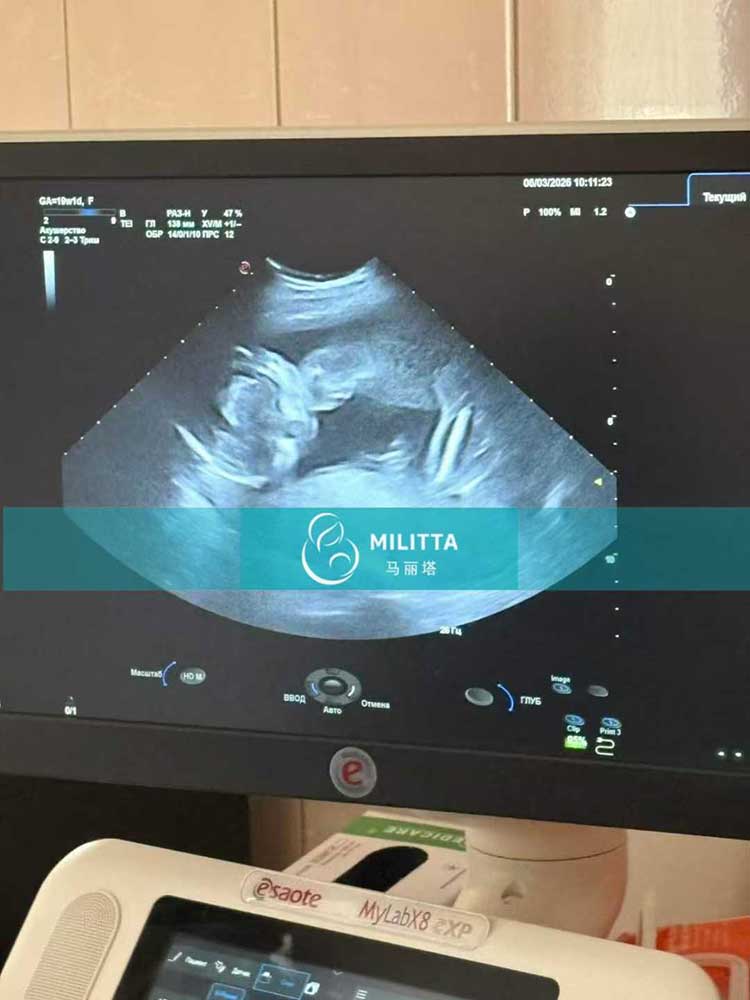

四个家庭在乌克兰生娃匹配的试管妈妈完成彩超与常规验孕产检

四个家庭在乌克兰生娃匹配的试管妈妈完成彩超与常规验孕产检,各项检查全部通过,胎宝宝发育一切正常!